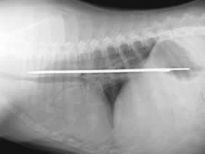

Şoke eden röntgen filmleri

Bu röntgen filmleri görenleri şaşkına çeviriyor!